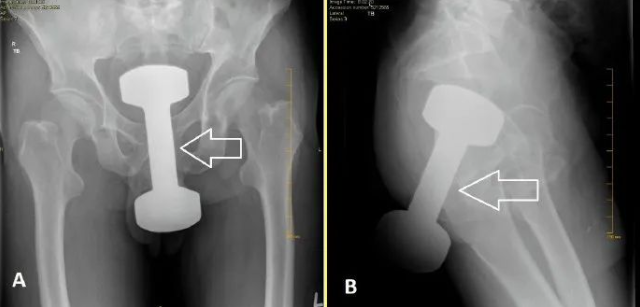

被塞进菊花的哑铃?

因为这些不该出现在直肠内的东西被称作是“直肠异物”或者“肛肠异物”,如果不及时清除,很有可能会导致直肠损伤、穿孔、感染和出血等严重后果。